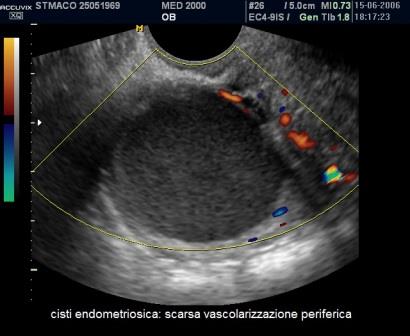

E' la localizzazione più frequente della patologia endometriosica rappresentando circa il 65% dei casi; gli aspetti ecografici più comuni delle cisti endometriosiche ovariche o endometriomi sono:

- cisti uniloculare o multiloculare con un massimo di 4 concamerazioni;

- contenuto "ground glass" ("a vetro smerigliato") legato all'accumulo di cellule ematiche che sfaldano dalla parete e di emosiderina;

- presenza di foci iperecogeni di parete;

- parete esterna della cisti spessa a superficie regolare;

- modesta vascolarizzazione di parete.

- il power doppler che consente di valutare la presenza di scarsa vascolarizzazione di parete e la assente vascolarizzazione delle aree di addensamento e delle irregolarità di parete;